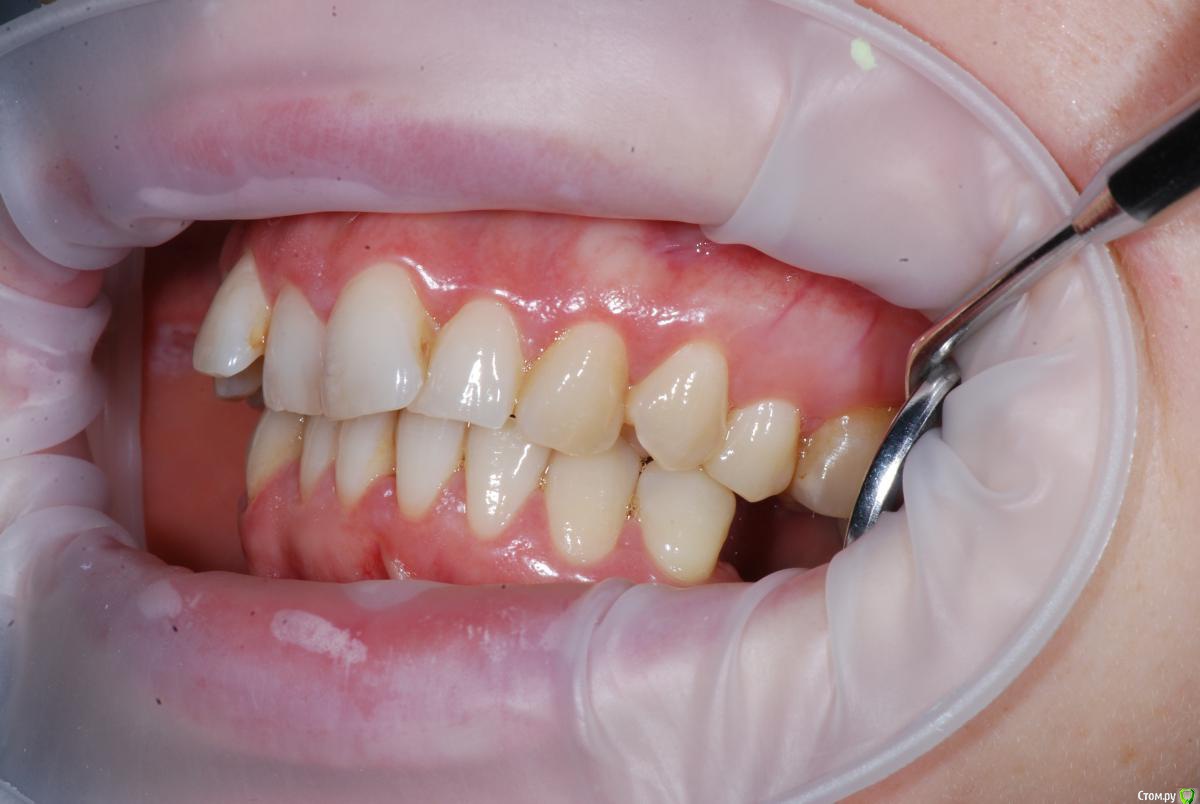

Afffinity Опубликовано 13 декабря, 2016 Автор Поделиться Опубликовано 13 декабря, 2016 Вот именно в чем в принципе сомневаетесь? и на моделях надо указывать анатомический центр, тогда сразу понятнее станет чего и куда и на сколько. ну Вы хотя бы свои мысли озвучили бы, расчет трг, характер асимметрии (в каком положении головки, что на КТ?) ... полностью Вам не распишут план, вопросы более конкретные попробуйте задать для коллегЕсли кратко то по расчетам ТРГ 2й скелетный класс, в цифрах завтра распишу. Прошу прощения что сразу не выложил. 2е, смущает смещение центральной линииПланируем установить систему Damon Q. Самый главный вопрос, возмножо ли в данном случае обойтись без удаления премоляров? Ссылка на комментарий